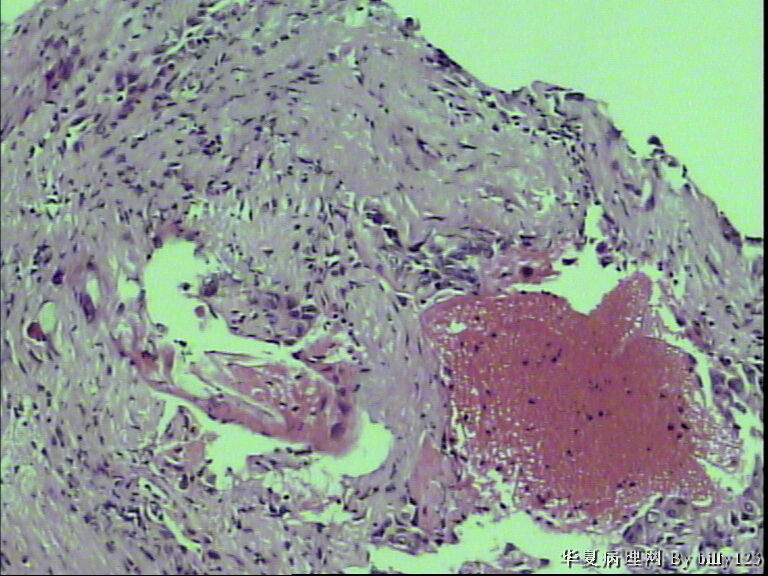

纤支镜活检,女性,75岁,请各位老师指教!

图3